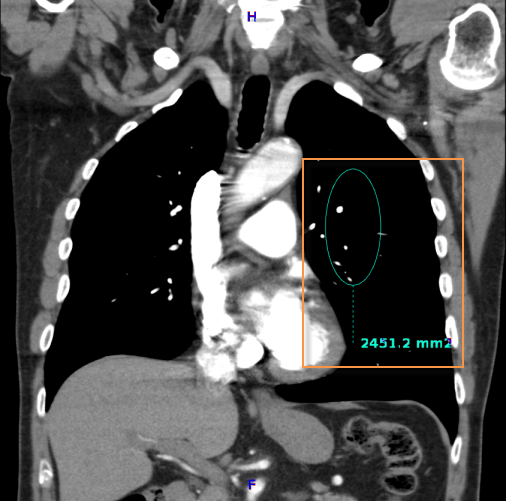

To obtain a region of interest measurement:

Select the Region of Interest ![]() icon

icon

Click on the region of interest

Drag on the mouse to encircle the area

Release the mouse button

Center

grab point  will move

ROI around the image and others will elongate or narrow.

will move

ROI around the image and others will elongate or narrow.